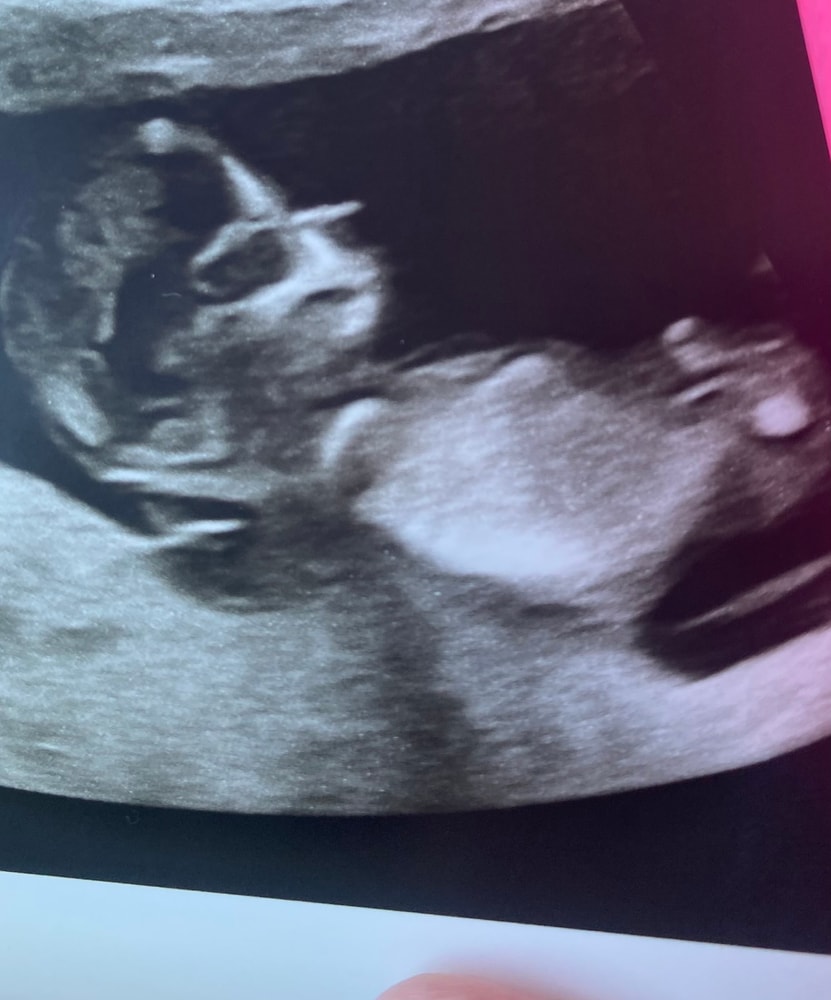

Я беременна,уже 13 недель,на 12-ой неделе врач осмотрел и сказал,что будет девочка,но засомневался,сказал что придёте на 20-ой неделе точно скажем.. Сможете по фото узи сказать пол? Заранее спасибо🫶🏻